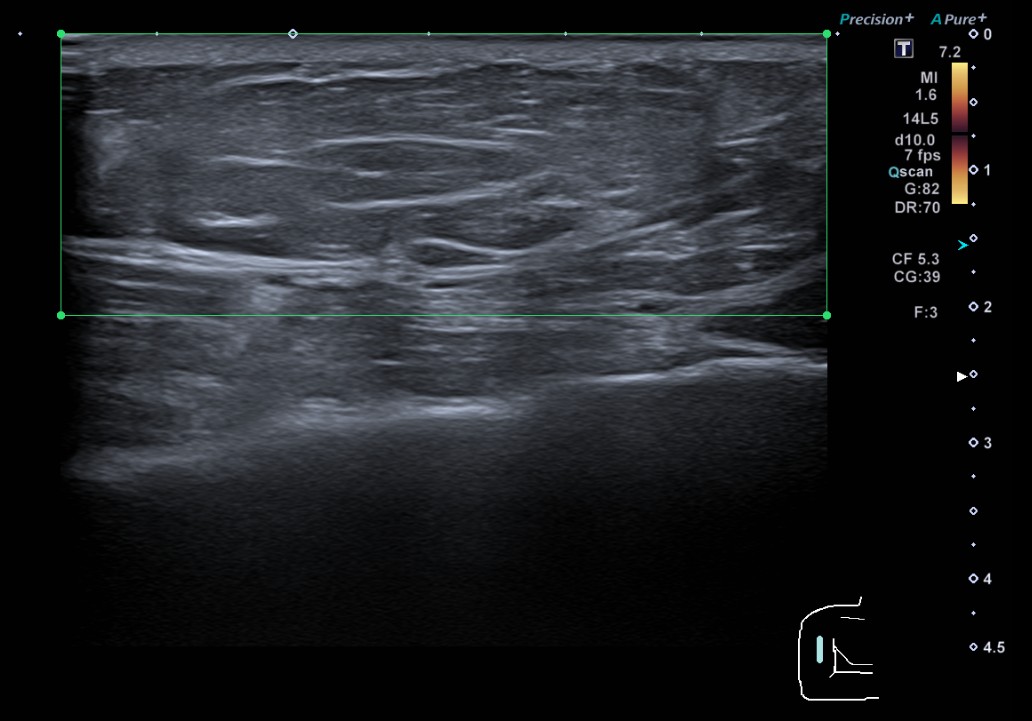

Descripción de los hallazgos ecográficos: formación nodular, isoecoica, de morfología ovalada y bodes delimitados, de un tamaño máximo de 40 x 31 x 12 mm, sugestiva de lipoma subcutáneo. En su interior, muestra dos pequeñas áreas de aspecto quistico, de 7 y 13 mm, sugestivas de áreas de necrosis grasa.

A las tres semanas el paciente acude a control y refiere mejoría del dolor. Se realiza de nuevo ecografía que no muestra cambios significativos.

Los lipomas son tumoraciones benignas que normalmente no son dolorosas y que raramente ocasionan ninguna complicación. La necrosis grasa, aunque poco frecuente, es una de las complicaciones que puede generar. La ecografía a pie de cama nos puede ayudar en el diagnóstico diferencial con otras tumoraciones cutáneas y para detectar possibles complicaciones de lesiones benignas, como en nuestro caso.